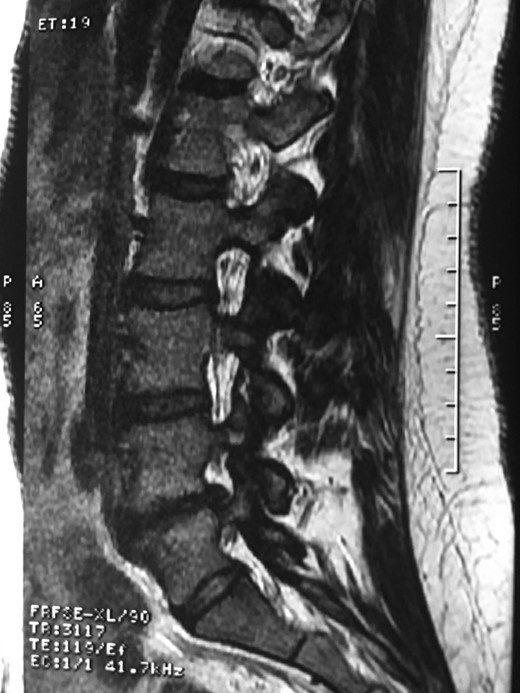

A 42-year-old female presented to the clinic with a history of chronic low back pain. She reported no relevant medical history. She had already been treated in the last 4 years by general practitioners with analgesics and home based physiotherapy with no satisfactory results. She had two previous admissions to the emergency department where morphine was prescribed to control the pain on her lower back. She was under ambulatory treatment with diclofenac, and tizanidine with partial relief of symptoms. Her main complaint was pain on the lower lumbar back with no radiation to the lower extremities. In her physical evaluation she presented limitation to full rotation and bending of the lumbar spine due to pain. Lasegue sign was negative, sensitivity, reflexes, sagittal balance, distal muscular strength and pulses were normal. Radiographs showed an overdeveloped left transverse process of the fifth lumbar vertebra which contacts with the sacrum at the left sacral wing with signs of degeneration at the same site (Fig. 1). Magnetic resonance imaging (MRI) studies were obtained (Figs 2–5). The patient was taken to the operating room where infiltration with 1 mL of lidocaine and 40 mg of Triamcinolone was performed in the pseudoarticulation between the left transverse process and the sacrum under fluoroscopic guidance. She reported a complete relief of pain after the procedure. At three months follow-up she was managed with strengthening and stabilizing exercises for the lumbar spine and postural education was initiated. She remains asymptomatic at her 12 months follow up.

Showing the protective effect of the limitation of the motion in the distal disc to the anomaly.

The partial fusion at the lower part of the lumbosacral transition produces important alterations in normal biomechanics at the levels immediately above and below the LSTV. Changes such as hypermobility and abnormal torque moments are present at the level above the LSTV, predisposing it to early degeneration (early disc pathology and facet joint degenerative disease). Restricted movement below the LSTV produces a protective effect against degeneration of disc and facets and is related to changes (facets are smaller and coronally oriented) in the dimensions of the lower level facet joints [7]. These alterations can be verified in the adjacent levels of the LSTV in our patient.